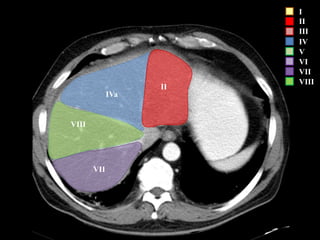

I

II

III

IV

V

VI

VII

VIII

IVa

I – Entre cava y porta

II – el más superior de los izquierdos

III – Por debajo del II

IV – por delante de la vesícula

V – por detrás de la vesícula

VI – relación con riñón derecho

VII – el más posterior de los segmentos superiores

VIII – domo hepático

Las claves de la segm. Hepática